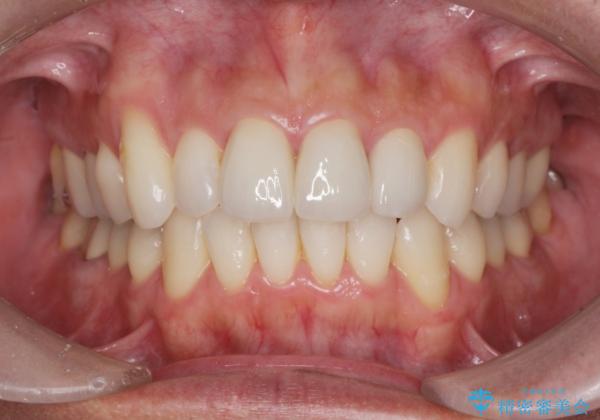

- 突き出た前歯の角度の改善と虫歯治療の改善を求めて来院されました。

虫歯を除去したのち、マウスピース矯正治療を行い、歯並びやがたつきを改善したのち、セラミックに置き換えることで審美性の向上を計画します。

矯正や虫歯治療、セラミック治療といった複合的な治療を一医院で行うことができるのが当法人の大きな特長です。